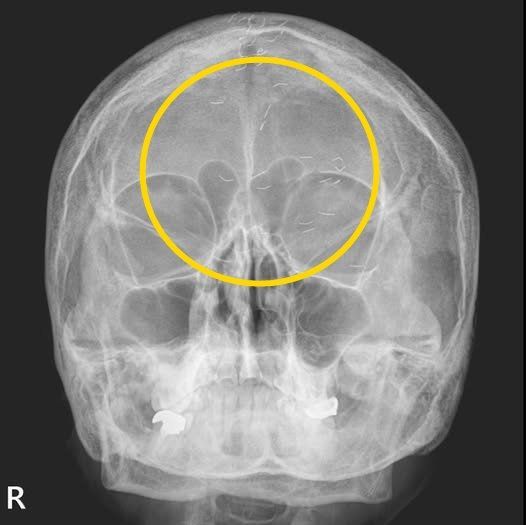

정의학과 전문의 양성관씨가 공개한 환자 엑스레이 사진. 양성관 씨 SNS 캡처 |

60대 한국여성의 머릿속에서 기생충처럼 보이는 이물질이 흩어져 있는 엑스레이 사진이 공개돼 화제다.

의사이자 작가로 활동하고 있는 가정의학과 전문의 양성관 씨는 최근 자신의 SNS에 ‘한국형 진료’라는 제목의 글과 사진을 올렸다.

양 씨는 “엑스레이에서 1cm 크기의 다수의 이물질이 발견됐다”며 “기생충인가? 전기칩인가? 외국이었다면 특이한 환자 사례로 ‘케이스 리포트’에 올랐을 것“이라고 말했다.

이어 “그러나 한국 의사들은 보자마자 헛웃음을 짓는다”며 “이물질의 정체는 ‘금침 요법’의 흔적”이라고 설명했다.

그러면서 “이물질이 무릎이나 허리에서 자주 발견되지만, 이번에는 머리에서 보였다”고 덧붙였다.

양 씨가 금침요법을 무수히 받아온 환자에게 내린 진단은 ‘긴장성 두통’이었다. 환자는 양 씨에게 ‘머리 중앙이 자주 아파 침 치료를 받고, 신경과에서 MRI도 찍었지만 이상이 없었다’라고 전했다.

양 씨는 해당 환자에게 “MRI와 MRA 검사 결과, 뇌출혈·뇌암·뇌경색 등의 이상 소견이 없었기에 긴장성 두통으로 확진했다”며 “이미 정밀 검사를 받았으니 너무 걱정하지 말라고 설명했다”고 한다.